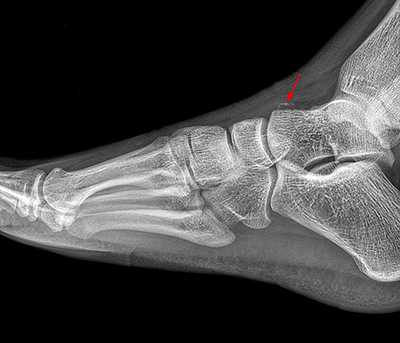

Рентгенологическое исследование

Для диагностики повреждения сустава Шопара делают рентген, КТ и МРТ. На передне-задней рентгенограмме определяют величину пяточно-кубовидного угла. Проводят одну касательную к наружному краю кубовидной кости и вторую касательную к наружному краю пяточной кости. В норме угол между касательными колеблется в пределах от 0 до 5°. Увеличение угла свидетельствует о нарушении стабильности пяточно-кубовидного сочленения. КТ во фронтальной и сагиттальной плоскостях позволяет выявить дефект суставных фасеток, смещение костей при вывихе и фрагментацию костей при переломе. КТ, по сравнению с рентгенографией, является более информативным методом диагностики. МРТ позволяет выявить дефекты отдельных связок.

Рис. 6. Отрывной перелом по тылу таранной кости на границе с суставом Шопара

Рис. 7. Перелом кубовидной кости по передней поверхности

Рис. 8. Переломо-вывих в суставе Шопара

Рис. 9. Переломо-вывих в суставе Шопара